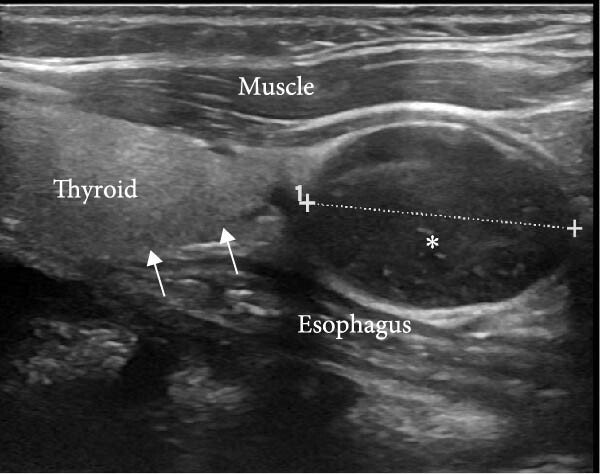

16-летняя девушка была направлена в эндокринологическую клинику стоматологом после случайного обнаружения кальцифицированной гранулемы пародонта. Сама пациентка не предъявляла никаких жалоб. В сыворотке крови были обнаружены высокие уровни кальция (14,2 мг/дл), ПТГ (944 пг/мл) и низкий уровень фосфора (2,3 мг/дл). Содержание креатинина составило 0,9 мг/дл. С помощью УЗИ была обнаружена аденома левой нижней паращитовидной железы (рис. 1-2), наличие которой подтвердилось при проведении сцинтиграфии паращитовидных желез с 99мТс-МИБИ.

Рисунок 1. Снимок продольного серо-шкального УЗИ левой доли щитовидной железы, на котором виден овальный гипоэхогенный узел размером 23 мм×17 мм×15 мм с четкими границами, прилегающий к нижнему полюсу левой доли щитовидной железы (стрелки).